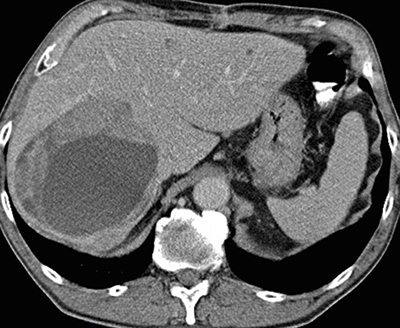

Figur 3. Karcinoidmetastas i levern. Delvis nekrotisk metastas före SIRT (selektiv intern radioterapi) (övre bilden). Oförändrad storlek av nekrotisk metastas 2 år efter SIRT-behandling (undre bilden).